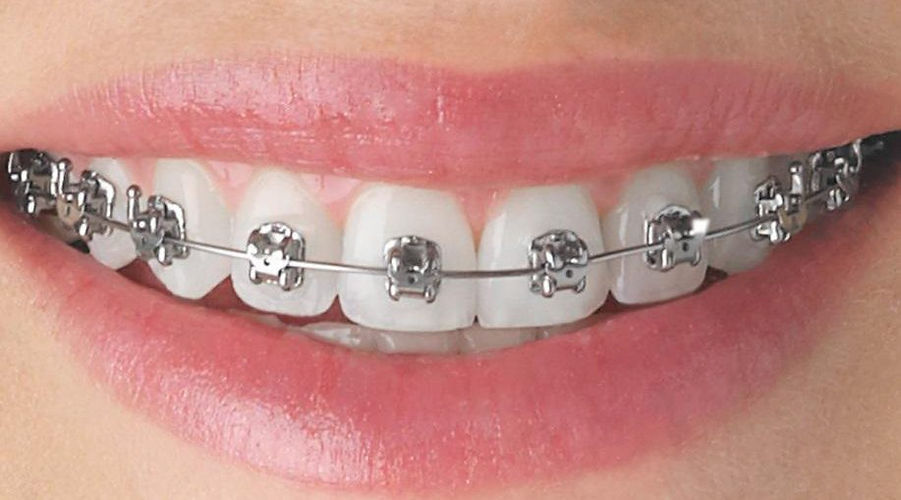

ORTHODONTIC TREATMENT

Orthodontic treatment will straighten the teeth or move them into a better position. This can improve the appearance and the way the teeth bite together, while also making them easier to clean.